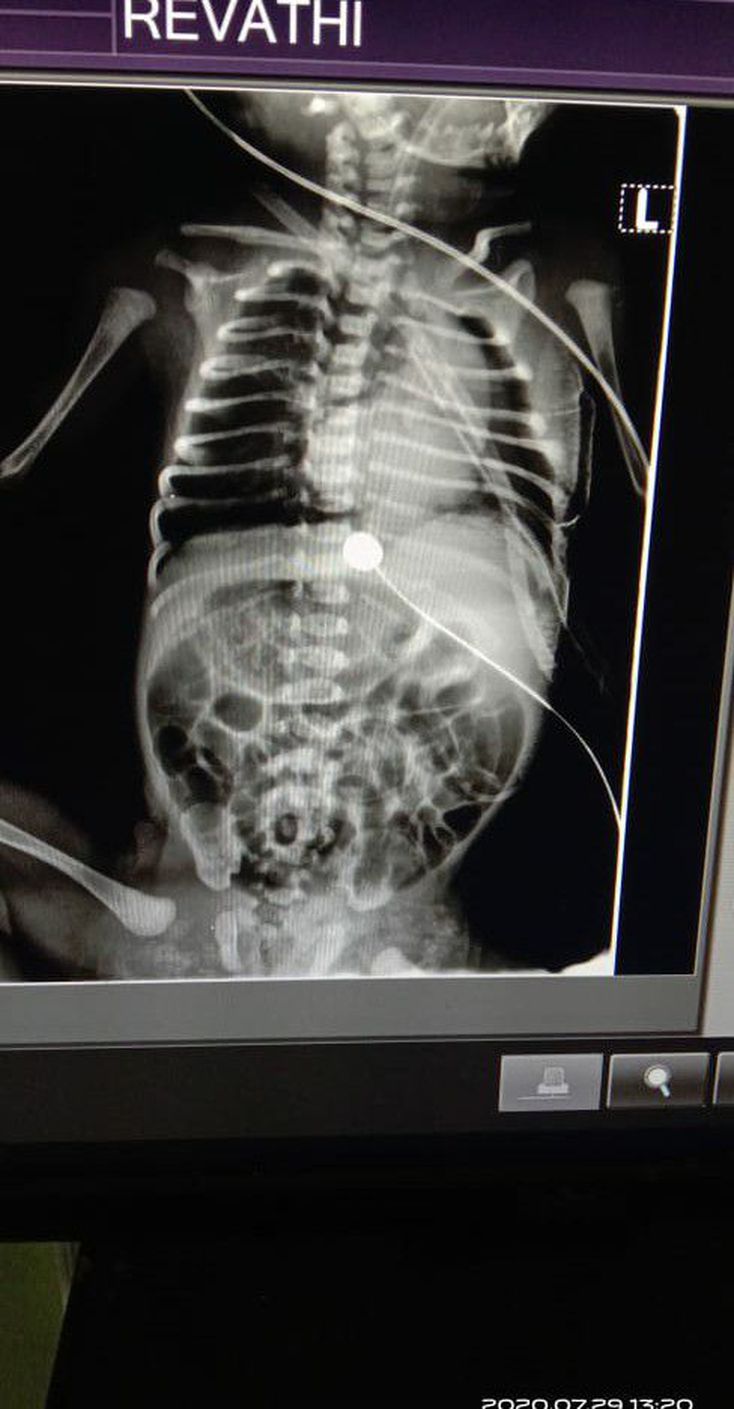

This body was born with oesophagus and traches combined....later doctor did surgery...this X ray was taken after surgery....interpretation pls?

The intubation tube and drain seen in x ray

Is the baby dextrocardia?